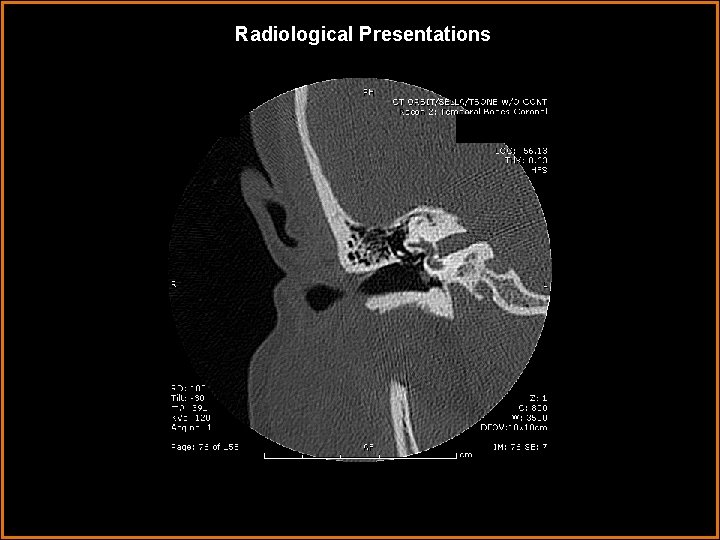

Findings and Differentials Findings: Soft tissue 5 mm nodule arising from the cochlear promontory in the middle ear. Clearly separated from facial nerve (its horizontal segment can be seen on the first several axial slices running anteromedial to posterolat, just under the lateral semicircular canal). Scutum intact, epitympanic recess clear. Differentials: • A. Glomus tympanicum • B. Cholesteatoma • C. Facial nerve schwannoma • D. Persistent stapedial artery

Discussion • Facial Nerve Schwannomas can arise in any segment of the facial nerve. They will typically expand the intraosseous canal. These images demonstrate normal sized IAC and no expansion of the intraosseus canal (arrow) containing the tympanic segment (which runs directly under the horizontal semicircular canal.